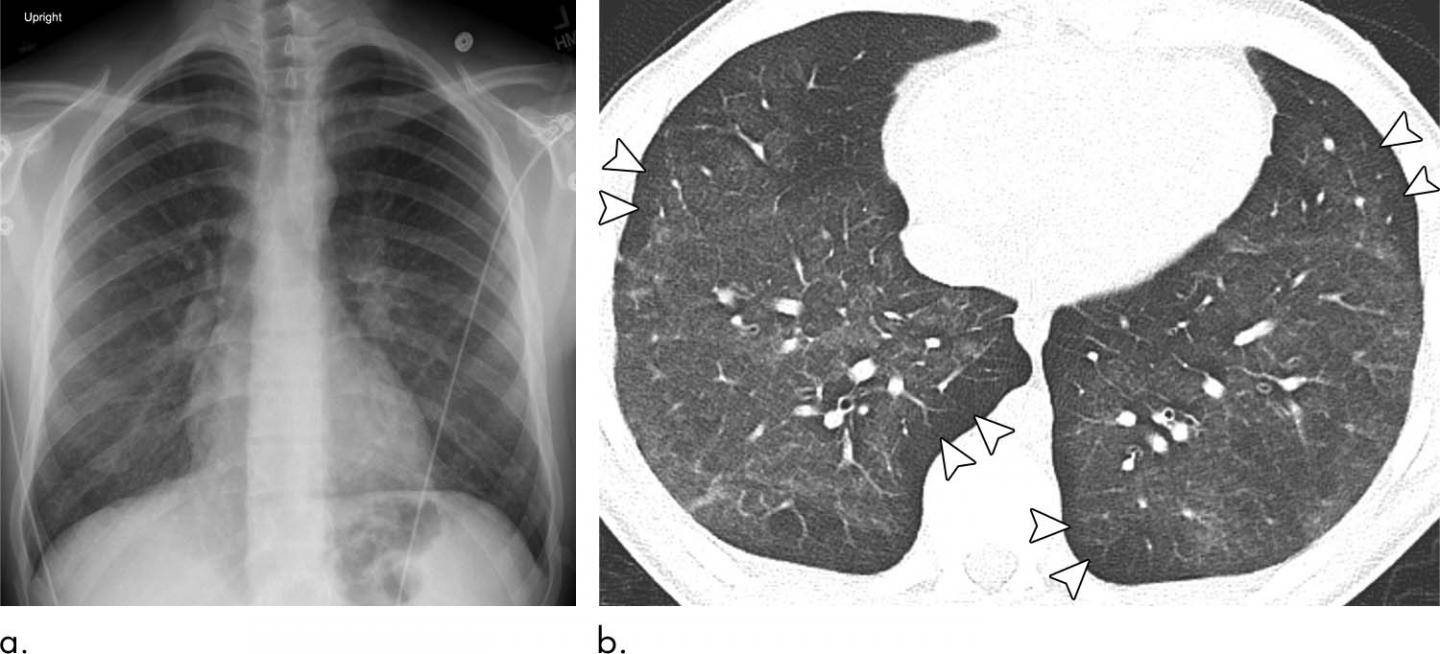

The results showed characteristic chest X-ray and CT findings. Bilateral and symmetric ground-glass opacity in the lungs, frequently associated with consolidation, often of lower lobe predominance, was the key imaging finding. On CT, subpleural sparing was also visualized in 79% of patients.

Dr. Artunduaga noted that chest X-ray alone does not allow the sufficient characterization of the patterns of EVALI in pediatric patients and, therefore, CT is needed for a complete assessment.

"CT provides a better evaluation of the extent and degree of involvement, as well as a better assessment of the characteristics of abnormal pulmonary findings. This can lead to the early diagnosis of EVALI, which would ultimately allow the timely management of this entity in the pediatric population," she said.